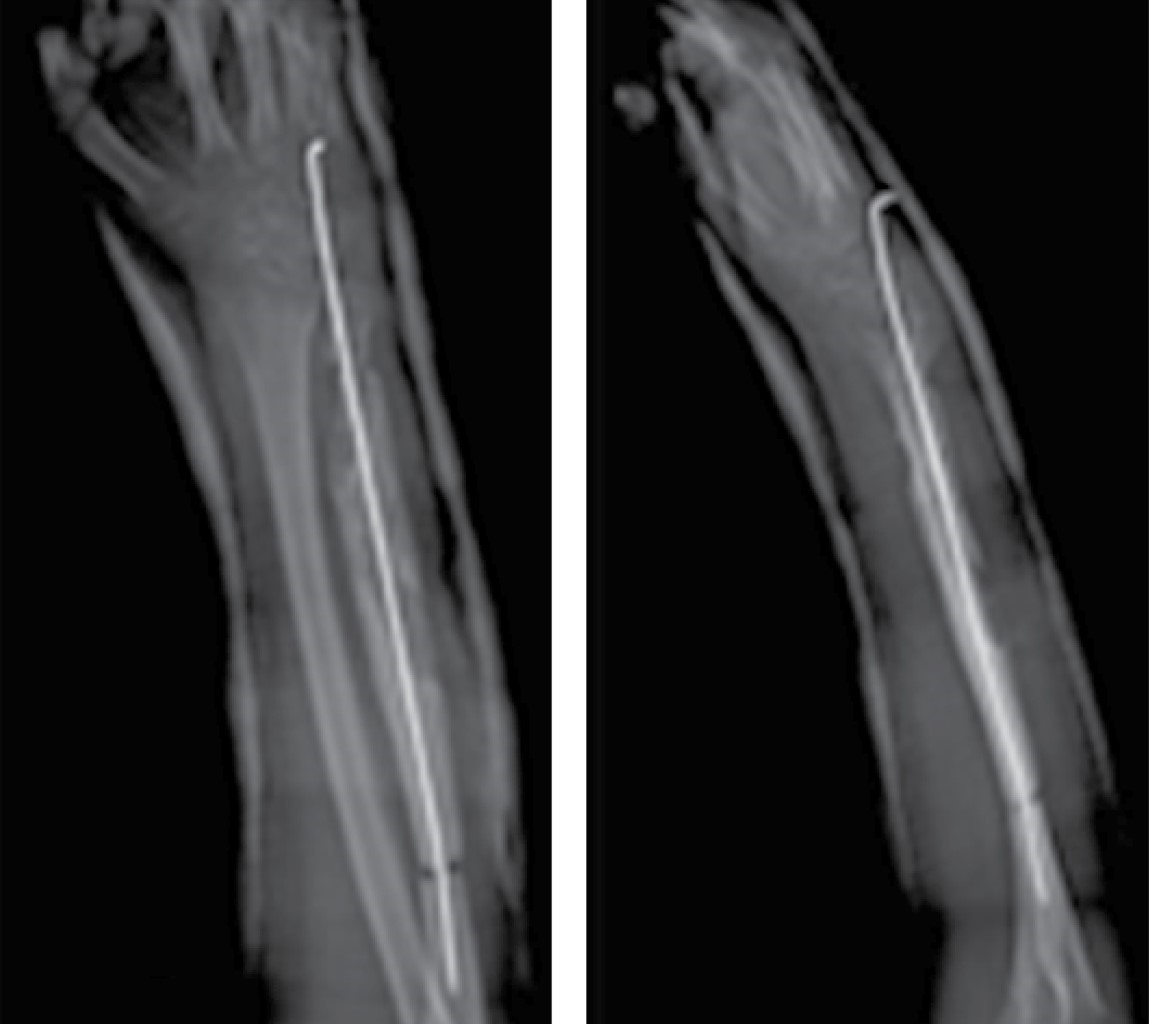

Figure 1

Figure 2

Figure 3

Figure 4

Figure 5

Figure 6

Figure 7

Figure 8